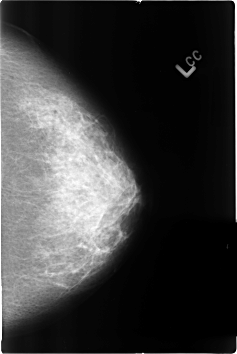

B_3142_1.LEFT_CC

LEFT_CC LINES 4600 PIXELS_PER_LINE 3080 BITS_PER_PIXEL 12 RESOLUTION 50 NON_OVERLAY